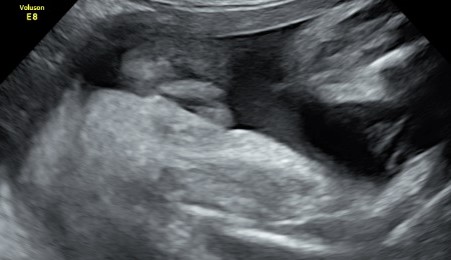

Il tesoro in ecografia è sempre più bello, infatti è da questo mese, ma soprattutto dal prossimo che comincerà ad ingrassare e diventare più tondetto per la gioia degli occhi di babbo e mamma!